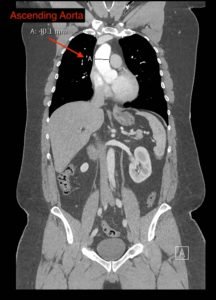

Point-of-care cardiac echocardiogram demonstrated a dilated ascending aorta (illustrated in red) measuring approximately 4 cm in the parasternal long axis (PLAX). A dilated aortic arch (illustrated in green) also measuring approximately 4 cm was appreciated using the suprasternal notch view (SSNV). A follow-up computed tomography angiogram (CTA) was performed, validating bedside ultrasound measurements.

The diagnostic criteria for dilated thoracic aneurysm is based on multiple factors including age, sex, and body size.2 An aortic root diameter of ³ 4.0 cm constitutes an ascending aortic dilation.3,4 Point-of-care cardiac and SSNV ultrasound of the thoracic aorta has been validated as an accurate study when performed by emergency physicians to identify thoracic aortic aneurysms (sensitivity of 71.4%, specificity of 100% when compared to gold standard of CTA). 5 This case is an example of the utility of rapid bedside diagnostic ultrasound, specifically the SSNV, in assessment of thoracic aneurysms.

Point-of-care cardiac echocardiography demonstrated a dilated ascending aorta. Finding a new thoracic aortic aneurysm in the setting of chest pain and hypertension is a “can’t miss” diagnosis due to the potential for rapid expansion leading to dissection and/or rupture.6 Point-of-care ultrasound utilizing the SSNV is a tool that can be used early in the evaluation of the patient that can help make quick determination of diagnostic plan and expedite initiating treatment in the emergency department.